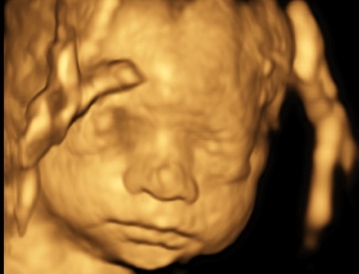

Cara 1